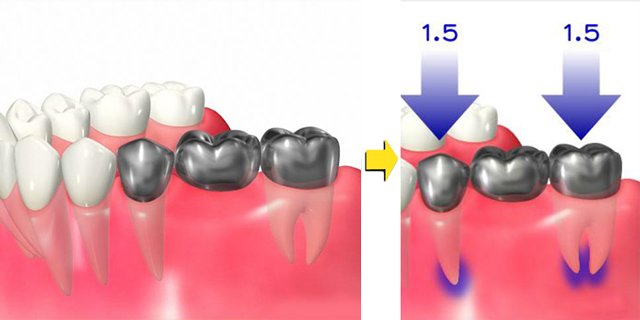

インプラント治療を行う部位には、インプラントが埋入できる骨の厚みが必要です。

歯を失ってしまう主な原因は歯周病や歯の根の病気の為、歯を失った部分は顎の骨も痩せ細ってしまい、

このままではインプラント手術ができないケースも少なくありません。

インプラントをするには周囲に十分な顎の骨の厚みが必要です

顎の骨が足りない場合、このままではインプラントはできません

このような場合は、骨造成手術(GBR)を行い、痩せ細ってしまった顎の骨の厚みを回復させてあげることでインプラント治療が可能になります。

骨が痩せてしまった場所に骨補填材を填入して骨の厚みを回復させることでインプラント治療が可能になります。

顎の骨が痩せてしまってインプラント治療ができるだけの十分な骨がない

骨造成を行うことでインプラント治療が可能になります